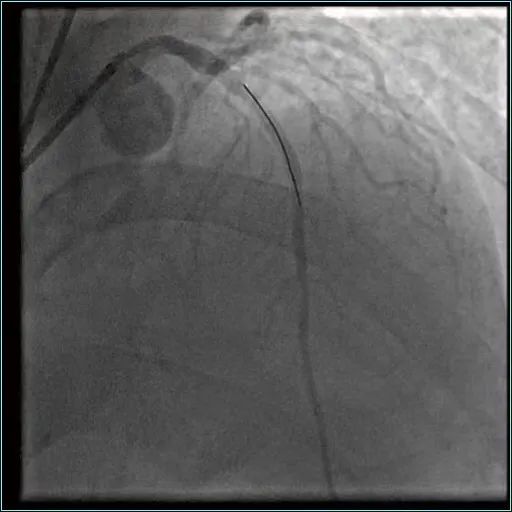

手术前

但是,刘先生除颤恢复心跳以后,非常烦躁不安、极不配合。而心脏手术精度极高,需要在一、两毫米的精细度上去操作。于是,麻醉科紧急麻醉、气管插管,送到导管室进行介入手术。心内科主任说:“如果血管闭塞超过半个小时,心肌就会出现大面积坏死,如果超过两到三个小时,心肌坏死大概要达到60%-70%,所以时间就是心肌、时间就是生命。一进入导管室,我们速度很快,大概10分钟就把血管打通了。”